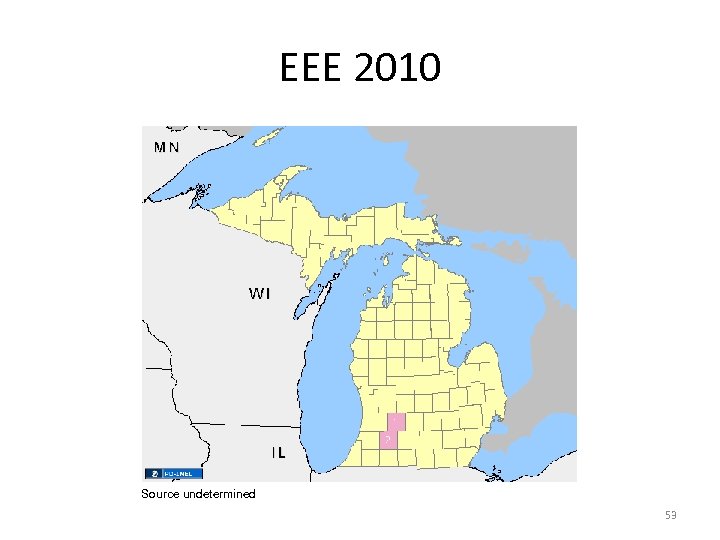

EEE 2010 Source undetermined 53